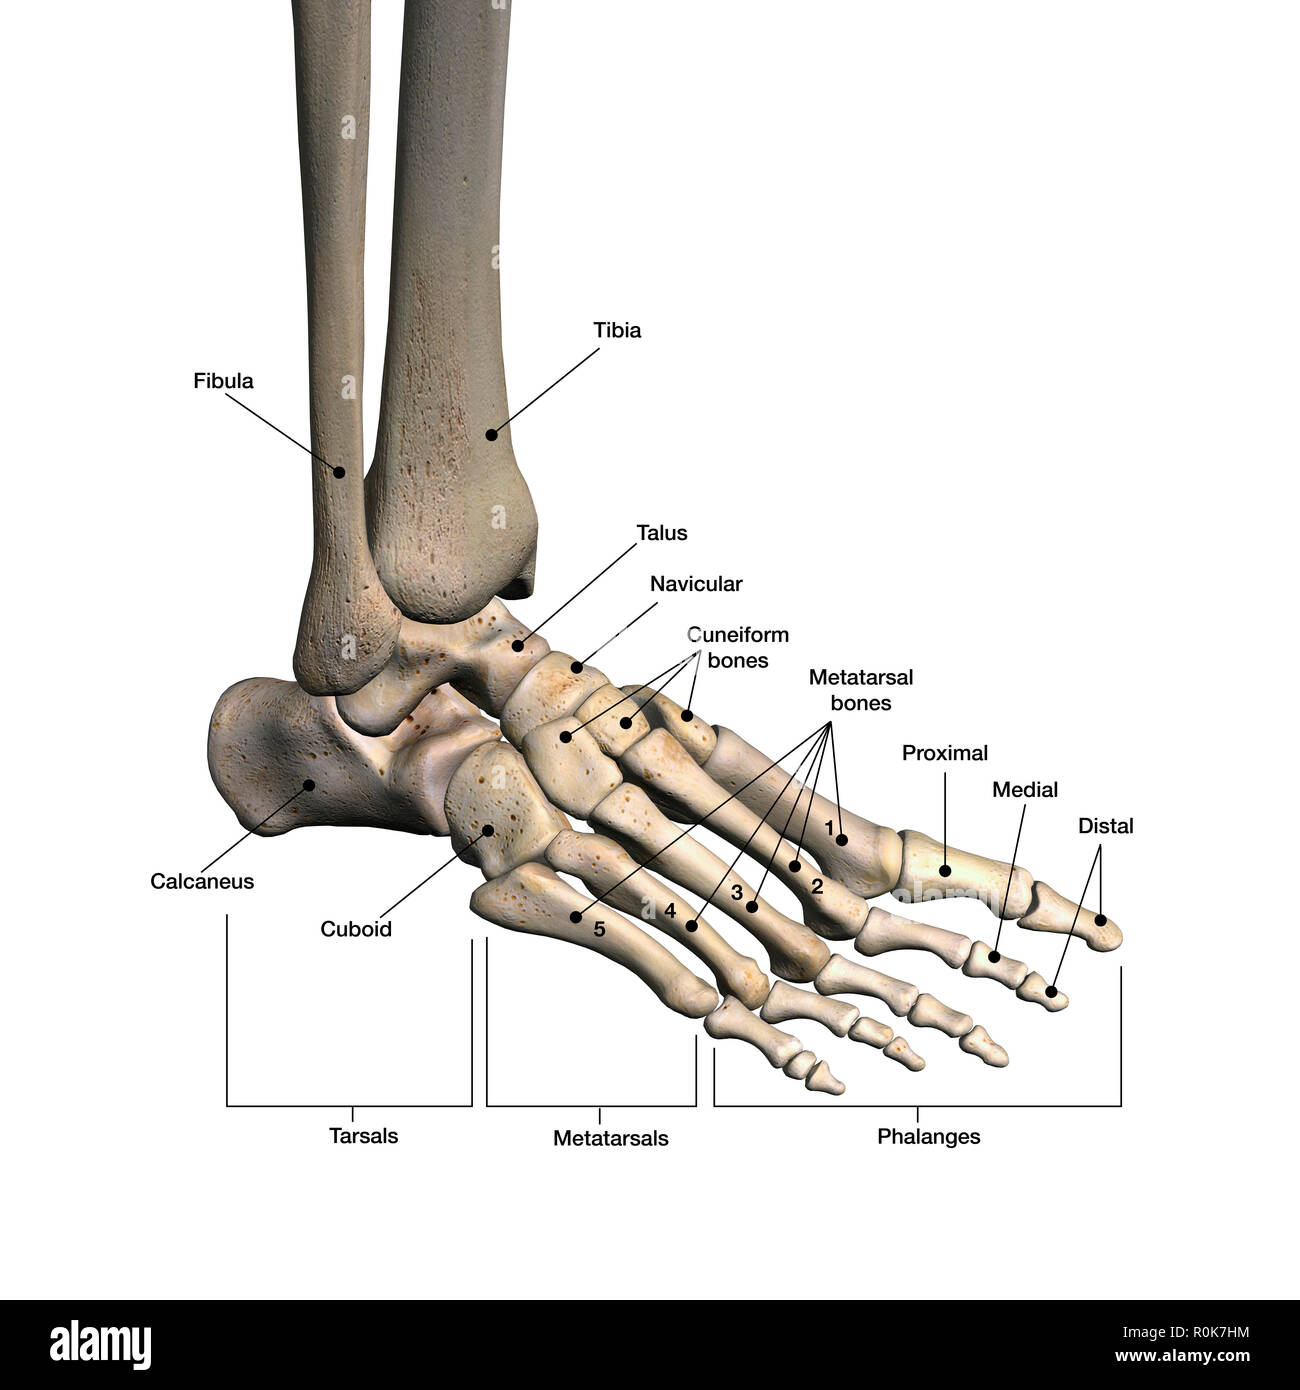

RF2DHMD0H–OS du pied. Anatomie humaine. Le schéma montre l'emplacement et le nom de tous les os du pied.

RMK228DY–Partie terminale du membre inférieur, reposant sur le sol au cours de posture droite ; le squelette du pied a 26 os.

RMK227XM–Partie terminale du membre inférieur, reposant sur le sol au cours de posture droite ; le squelette du pied a 26 os.